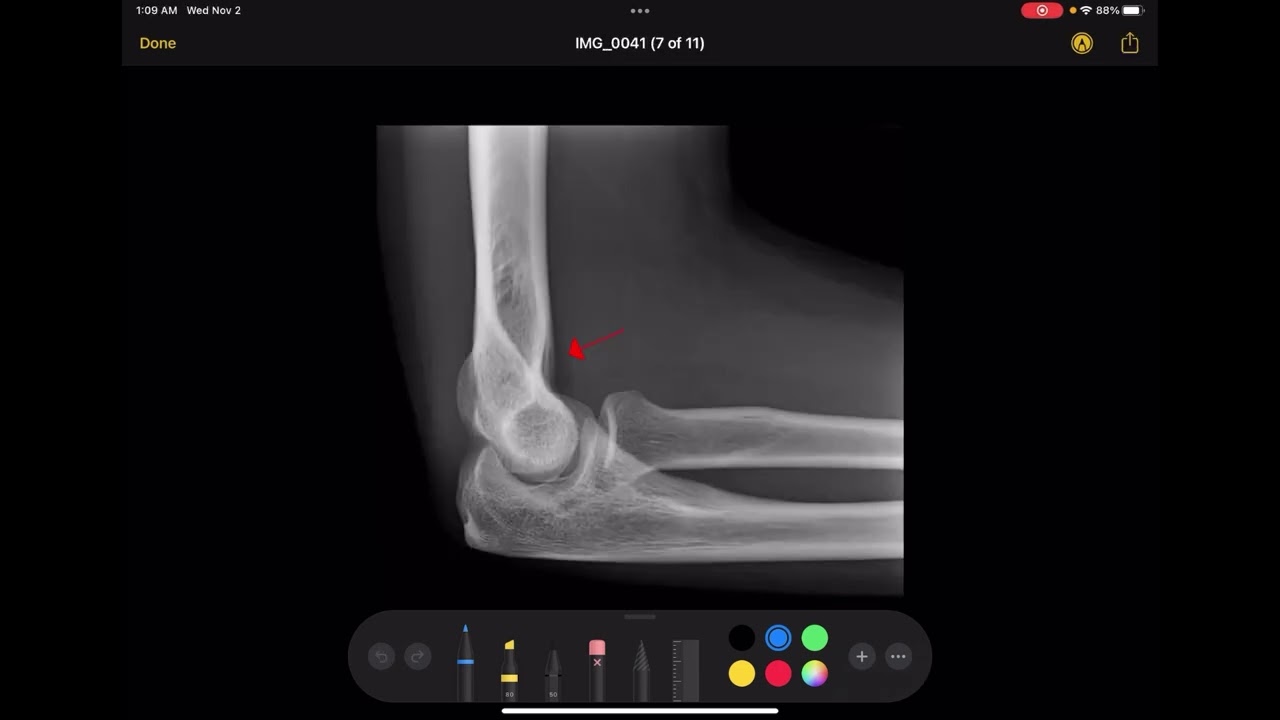

X-ray Positioning Evaluation - Lateral Elbow

What's your favorite name for a radiographic sign?? Put it in the comments! Thanks to WikiRadiography: http://www.wikiradiography.net/page/E... Shout-out to BSQUARED's MUSICAL THINGS - Check out "I Count By 5s" and subscribe to their channel for excellent creative content for kids!    • I count by 5s   Two Months to Mastery Audiobook is out on Audible! https://amzn.to/3kFEPSO It's also available on Google here: https://play.google.com/store/audiobo... FREE STUFF! Receive a complimentary copy of 53 Free Questions: Volume 1 - Patient Care here: https://mailchi.mp/557c2d18428e/53fre... COOL BOOKS! Rock the Registry - Volume 1: https://amzn.to/2XPgfoW Time, Distance, and Shielding - A Female Protagonist Series of Suspense Thrillers - https://amzn.to/3iSA72q MORE VIDEOS! For more information check out the videos on the Golden Formulas: Part 1 is here:    • X-ray Golden Formulas - Part 1   Part 2 is here:    • X-ray Golden Formulas - Part 2   PLAYLISTS! Full image production playlist: https://www.youtube.com/playlist?list... Full CT Playlist: https://www.youtube.com/playlist?list...